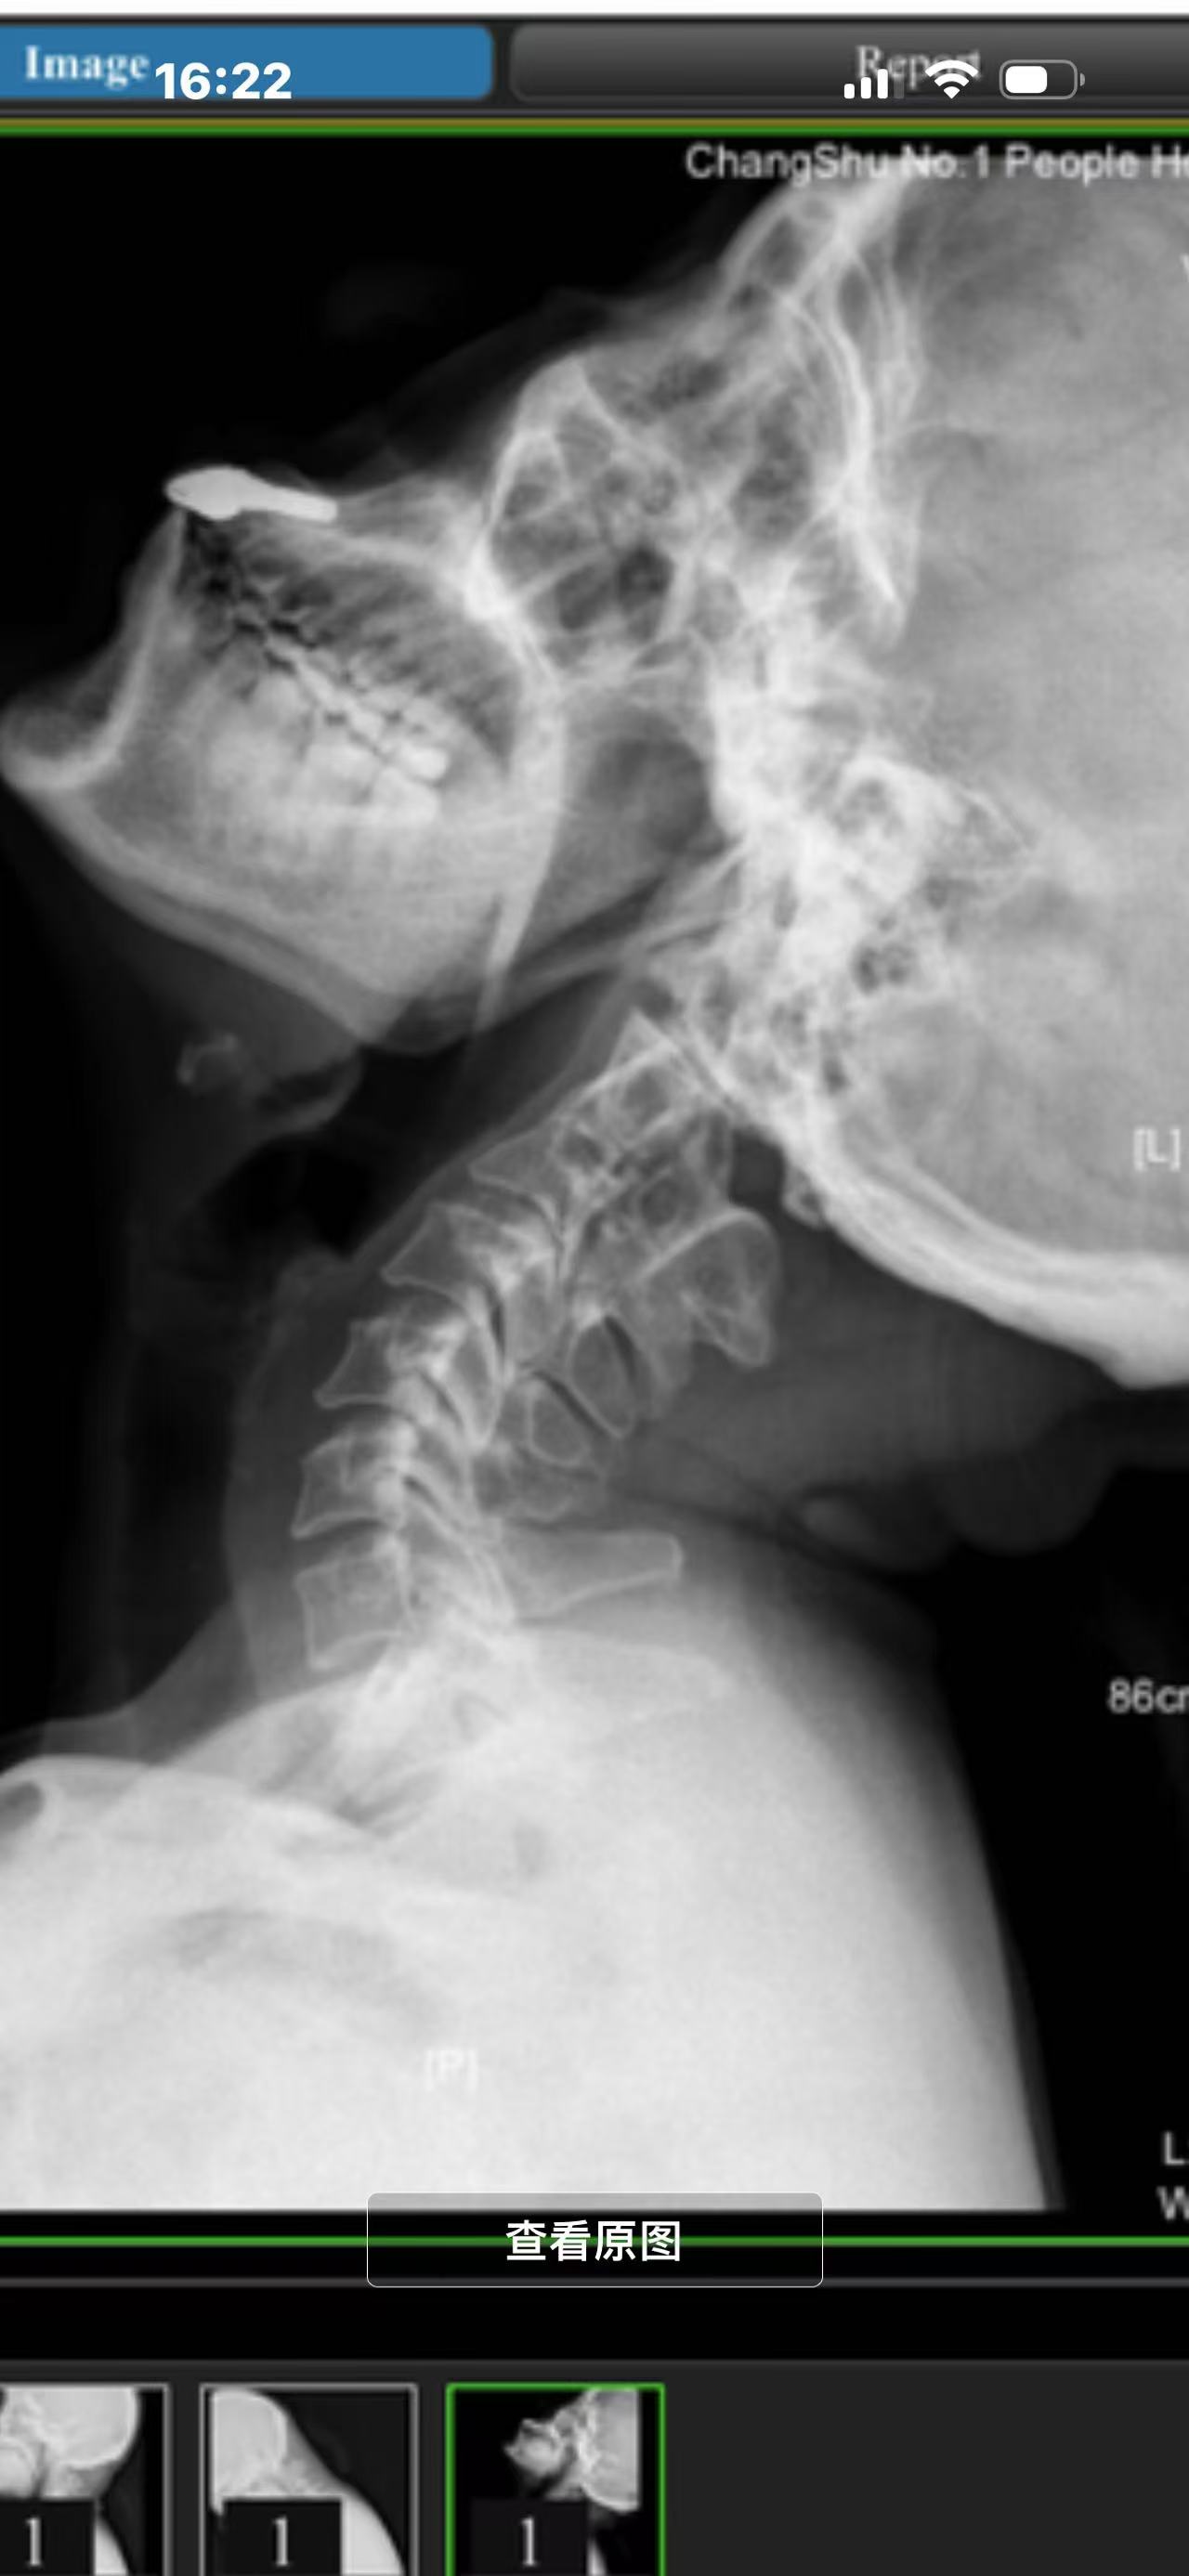

• 症状:颈重,肩重,肩甲骨经常火辣辣的,头前伸寰枢椎那会嘎嘎响

• 诊断:寰枢椎脱位,颅底凹陷

• 2024.02.27,复查,对位良好,偶尔会肩甲骨酸,坐下就不酸。